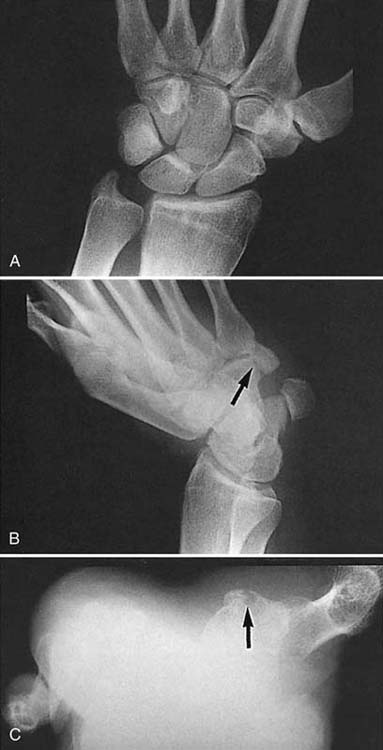

Figure 13-12 Fracture of the trapezial ridge. A, This routine posteroanterior view of the wrist is normal. B, A supinated oblique view shows a fracture of the trapezial ridge (arrow). C, A carpal tunnel view in the same patient also demonstrates this type of fracture (arrow).

images

Figure 13-13 Carpal tunnel view showing a fracture of the hook of the hamate (arrow).